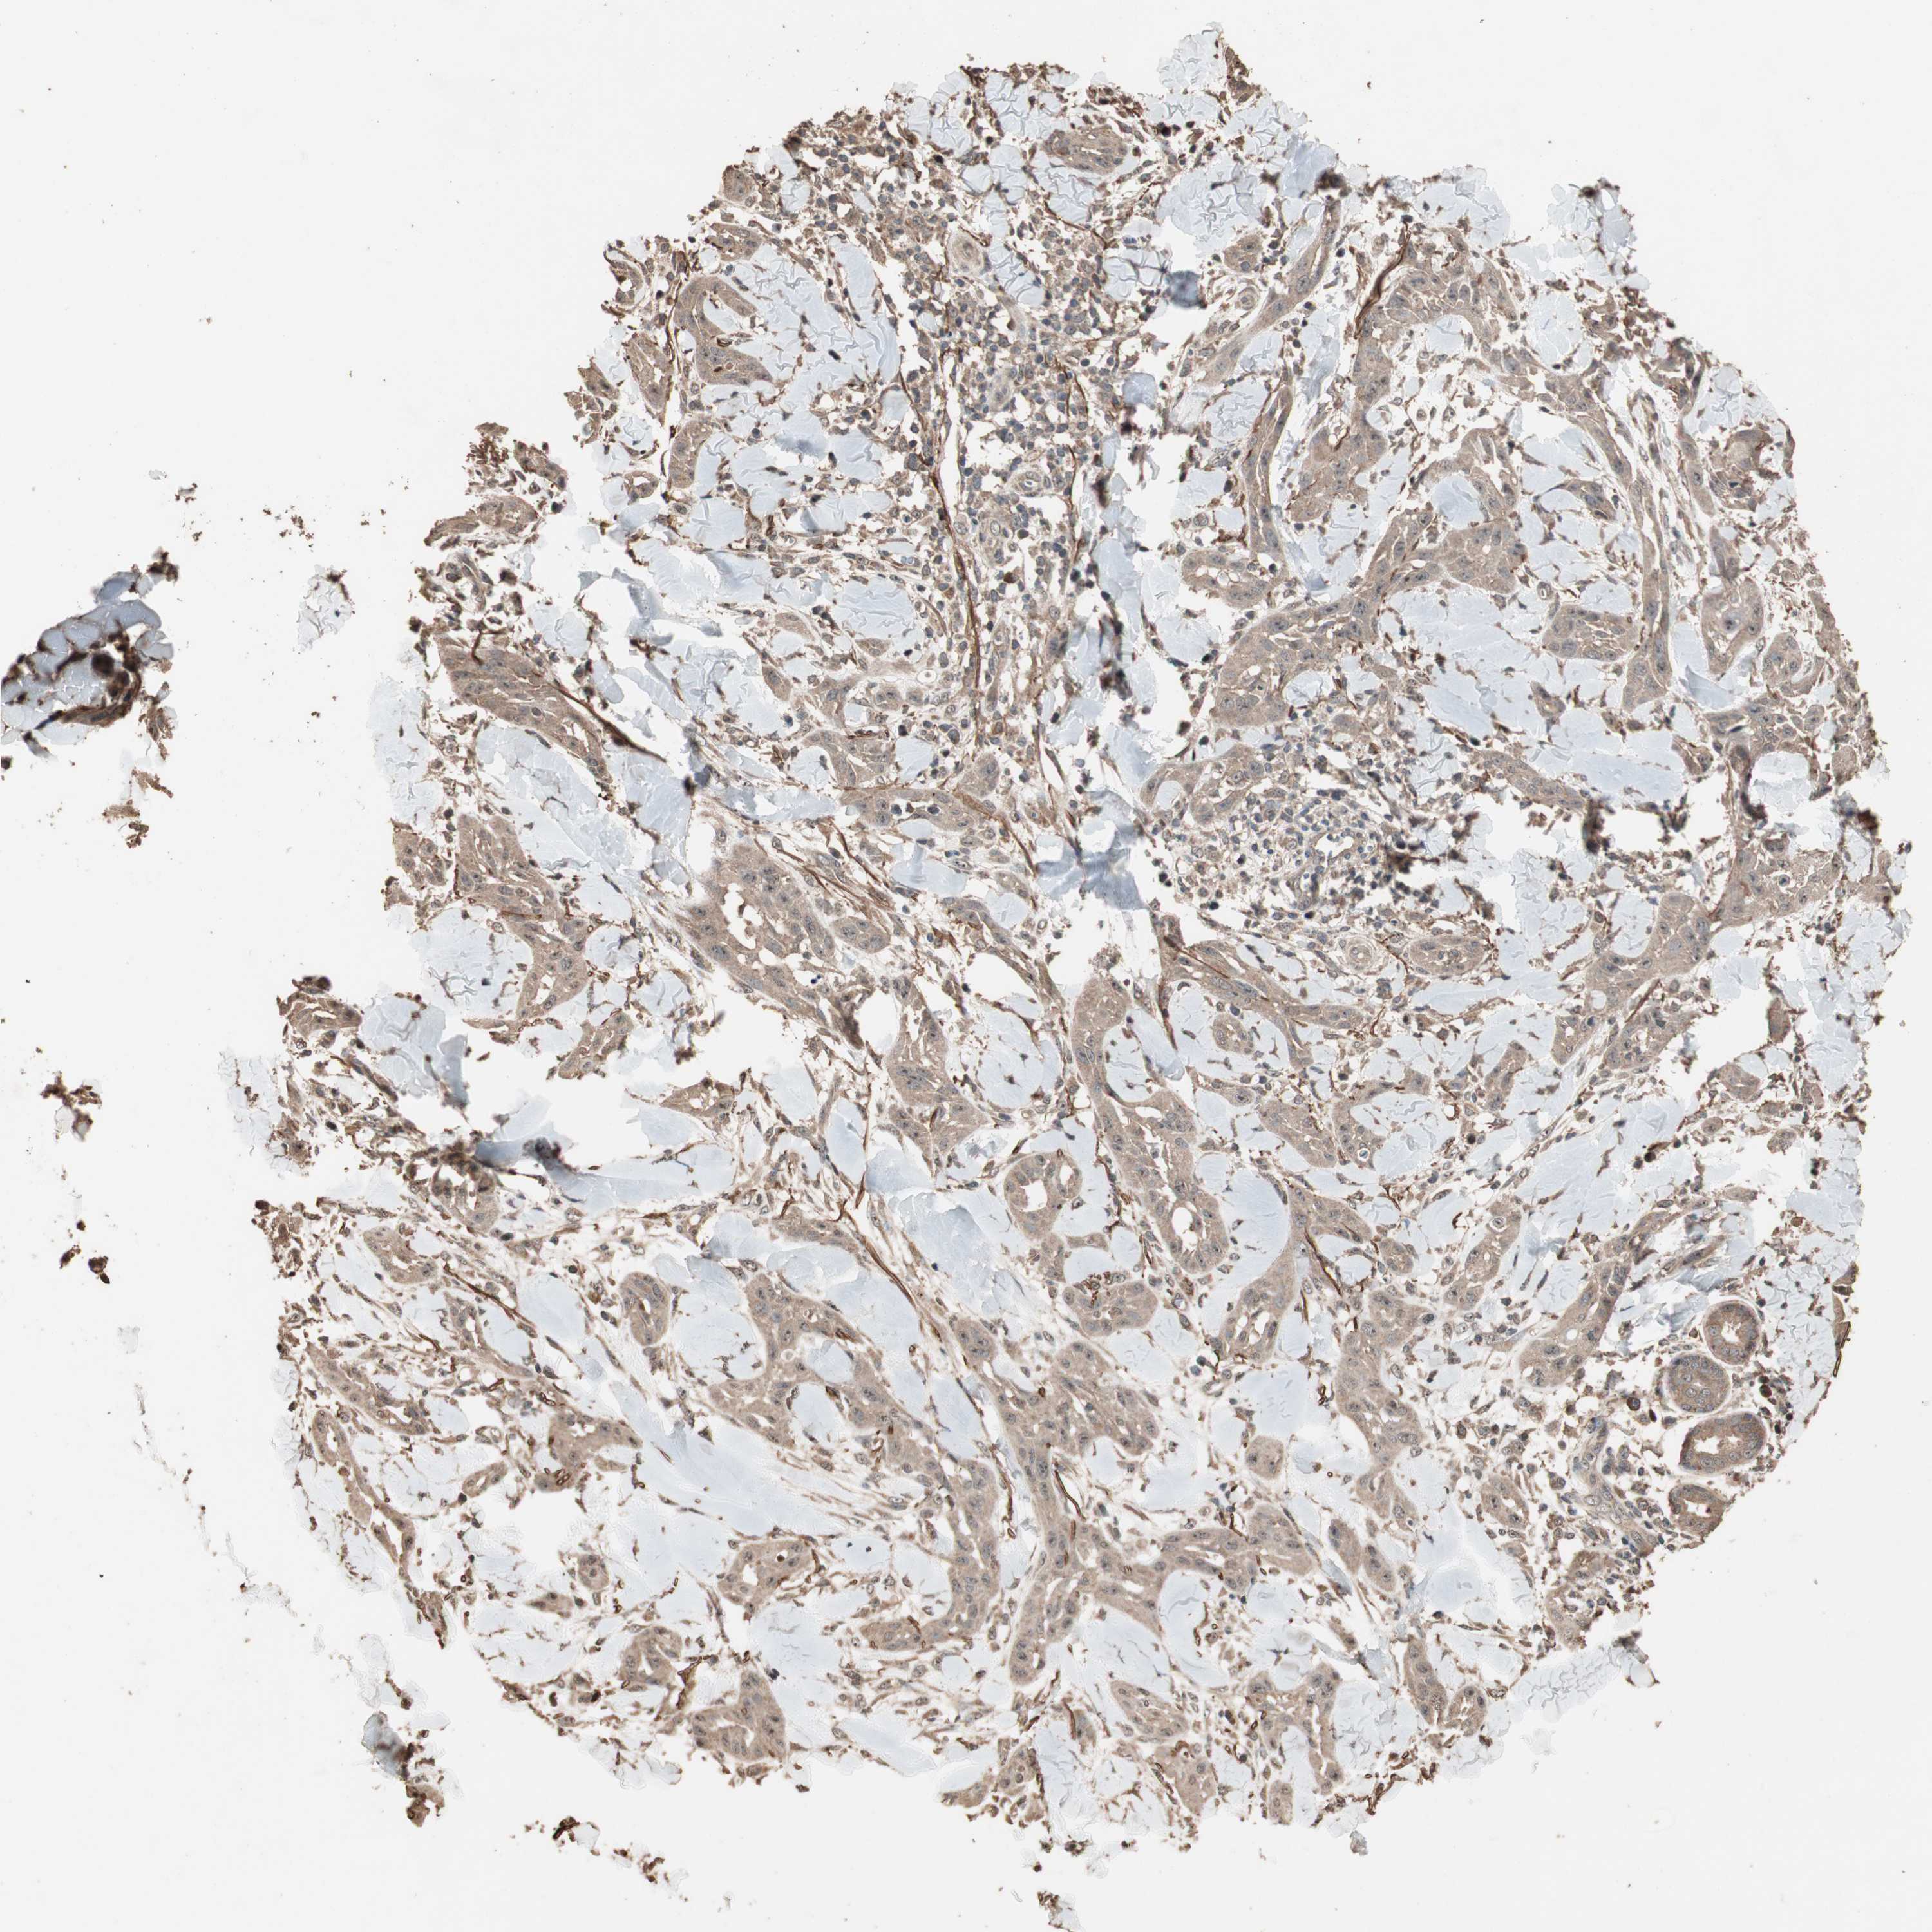

SKIN CANCER - Protein expressioni

A mouse-over function shows sample information and annotation data. Click on an image to view it in a full screen mode. Samples can be filtered based on level of antibody staining by selecting one or several of the following categories: high, medium, low and not detected. The assay and annotation is described here.

Each image is clickable and will lead to virtual microscopy that enables deeper exploration of all samples and also displays staining intensity scores, fraction scores and subcellular localization as well as patient and tissue information for each sample.

Antibody HPA006287

Staining

High

Intensity

Strong

Quantity

>75%

Location

Nuclear

Squamous cell carcinoma, NOS